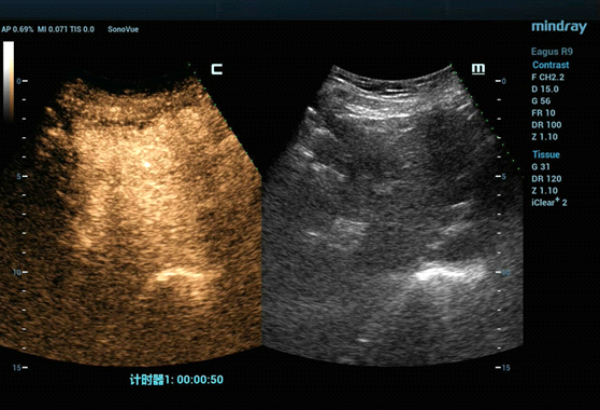

The S4 tumor seen on abdominal CT could not be demonstrated on conventional gray-scale ultrasound imaging. On contrast-enhanced ultrasound (CEUS) the lesion demonstrated hypervascularity in the arterial phase (Fig. 2) with iso-enhancement in the portal and late phases (Fig. 3).

The tumor was isoechoic and could not be clearly displayed using 2D grayscale ultrasound, therefore using conventional ultrasound guidance alone could result in inaccurate positioning and incomplete ablation. However, Fusion Imaging combining real-time ultrasound with the contrast-enhanced CT dataset allowed for accurate antenna positioning and successful treatment of the lesion by percutaneous MWA. CEUS was used pre-procedure to confirm tumor location and post-procedure to evaluate the ablation zone and ensure the efficacy of the treatment.